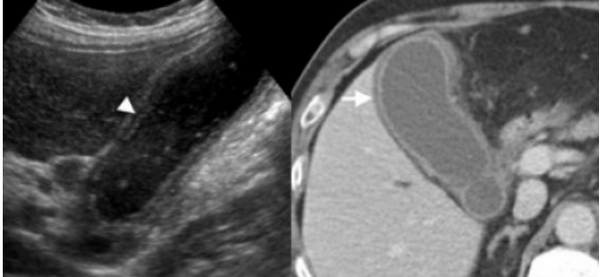

Острый калькулезный холецистит. После контрастного усиления визуализируется растянутый желчный пузырь (белые наконечники) со слегка утолщенной стенкой. Визуализируется камень в шейки желчного пузыря (белая стрелка).

Сверху изображения пациента 62 лет с калькулезным холециститом. На УЗИ визуализируется стенки желчного пузыря растянутые, с субсерозным отеком (указано белыми стрелками) и в просвете желчного пузыря камень и взвесь. На КТ визуализируется переход воспалительного процесса с желчного пузыря на соседние ткани (перихолецистит).